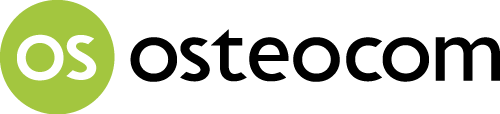

Εικ. 2

Ακριβής προσδιορισμός του χρώματος των δοντιών με Vita Toothguide 3D Master.

Εικ. 3

Το καθορισμένο βασικό χρώμα 2Μ2 καταγράφηκε και λήφθηκε μία ψηφιακή φωτογραφία.

Εικ. 4

Λήφθηκε μία φωτογραφία του βασικού χρώματος τοποθετημένου δίπλα στο μη αποκατεστημένο κυνόδοντα…

Εικ. 5

…και λήφθηκαν περισσότερες φωτογραφίες σε διαφορετικές γωνίες προς την οδοντοφυία για να ληφθούν όσο το δυνατόν περισσότερα δεδομένα για το εργαστήριο.